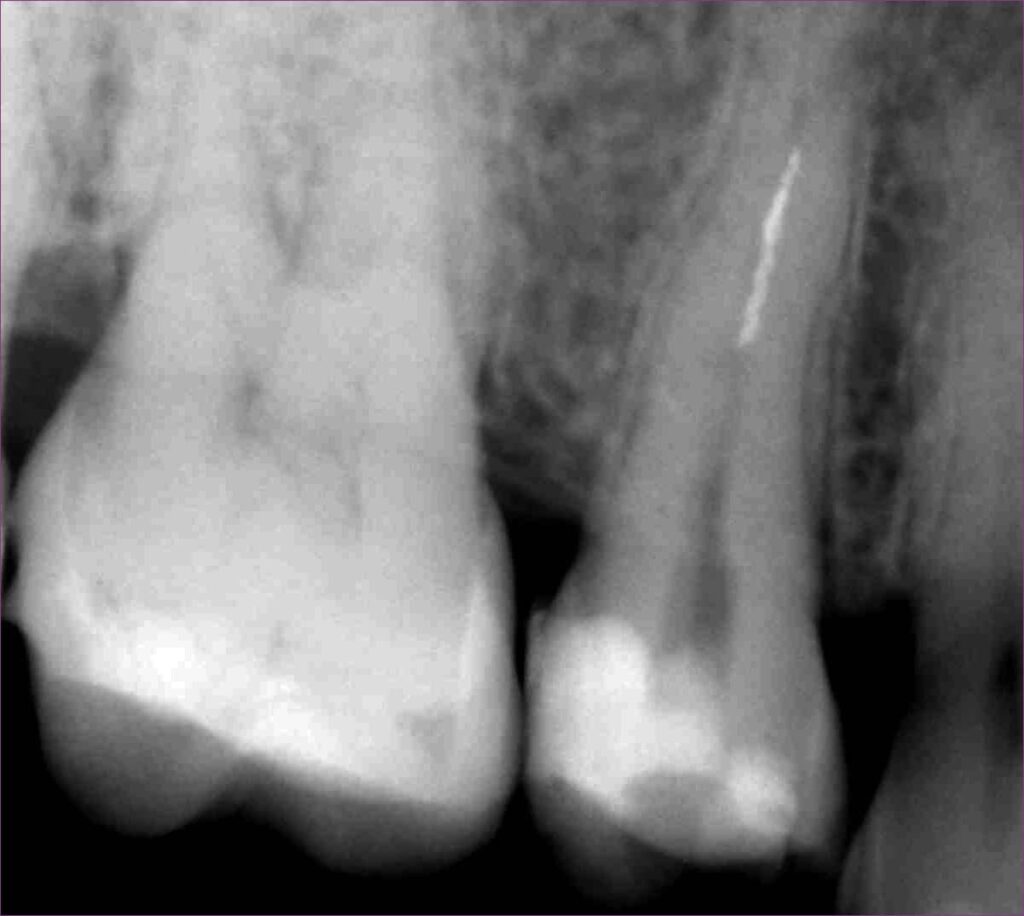

Az érintett jobb felső ötös fogról a páciens már egy kis fogfelvétellel érkezett. A kezelés megkezdése előtt a röntgen megtekintésekor feltűnt, hogy valószínűleg nem egy, hanem két betört fragmentumról van szó. Ezek a fogak gyakran két csatornával rendelkeznek, illetve ebben az esetben egy érdekes variációval: a két csatornának közös vége van. Ilyenkor az egymás felé ívelő gyökércsatornák meglehetősen görbék lehetnek - tipikus helyei a tűtöréseknek.

Először a szájpadlás felőli gyökércsatornában tártuk fel a tűt. Óvatosan, a megfelelő technikát alkalmazva sikerült eltávolítani a kb. 4 mm-es darabot. Ilyenkor készítünk egy kontrollröntgent, hogy lássuk, valóban nem maradt bent semmi az eltávolított tűből. Ekkor vált biztossá a gyanúnk, van még egy műszer a fogban.

mikroszkópos gyökérkezeléssel megmentett fog: a bent rekedt fragmentumok eltávolítása 2